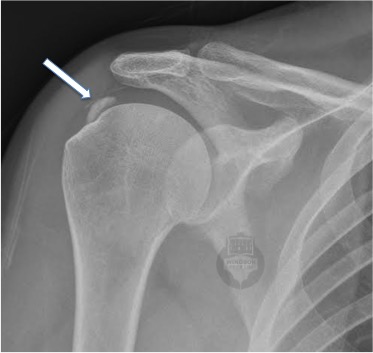

Calcium deposit in the Supraspinatus rotator cuff tendon  - white arrow